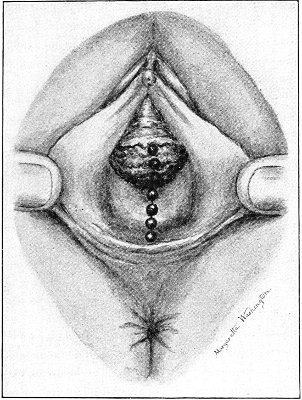

The secondary operation is performed at any time after cicatrization has occurred—often many years after the receipt of the injury. This operation is at present one of the commonest in gynecology, because the injury is not detected, is neglected, or is improperly repaired after labor. In the secondary operation an anesthetic is necessary. The mucous membrane must be removed or denuded on the posterior wall and about the mouth of the vagina, in order that the lacerated structures may be brought again in apposition. The denudation is best made by means of scissors curved on the flat (Figs. 24 and 25).

The strip of mucous membrane to be removed is picked up with a tenaculum (Fig. 26) or with tissue forceps 65 (Fig. 27); the scissors are placed with the blades parallel to the surface to be denuded, and the strip is cut away evenly, in one piece if possible. A similar contiguous strip is removed, and so on until the necessary surface is bare. Sponges in holders (Fig. 28) or continuous irrigation may be used to remove blood.

The sutures may be fastened by passing the ends through a perforated shot which is slipped down to the line of union and compressed by the shot-compressor (Fig. 32). All blood should be carefully removed from the surfaces that are brought together. The sutures should only be sufficiently tense to produce accurate apposition. A light gauze drain should be introduced in the vagina, and should be removed in forty-eight hours. Afterward one vaginal douche of about a quart of warm bichloride solution (1:2000) should be administered every day. After the douche the labia should be separated and the vagina carefully dried by cotton held in dressing-forceps. Except in those cases in which the sphincter ani is involved, the bowels may be moved on the second or third day. The woman should stay in bed for two weeks, at the end of which time the sutures should be removed. 67 She should avoid heavy lifting, long standing, and bicycle- or horseback-riding for two months after the operation. Constipation should always be avoided. Coitus may be resumed six weeks after operation.

Slight Median laceration of the Perineum.—In this injury the tear takes place through the fourchette. Posteriorly it may extend as far as the sphincter ani muscle. Upward it may extend for an inch up the posterior vaginal wall. The appearance of this tear is shown in Fig. 33. It will be noted that, as this tear takes place in the median line, none of the muscles that support the perineum are involved, nor are the planes of fascia injured. The perineum is slightly split, and the insertions and origins of the muscles and the fascia are slightly separated. The supporting structures of the perineum and the pelvic floor are, however, uninjured.

Fig. 33.—Recent slight median laceration of the perineum: sutures introduced.

If this tear is detected after labor, it should be closed by the immediate operation. A slight tear involving chiefly the cutaneous aspect of the perineum should be closed by three or four sutures introduced from the outside, as in Fig. 33. The needle should be introduced about a quarter of an inch from the edge of the wound. It should not be passed parallel with the plane of the lacerated surface, but should be swept outward and then inward toward the 68 angle at the bottom of the tear (Fig. 34). It may either emerge at the angle and be re-introduced, or it may be passed directly through to the skin-margin on the opposite side of the wound. If the suture is passed in this way, there will be perfect apposition throughout the whole surface of laceration. If the sutures are improperly passed, there may result only apposition of the skin-edges.

Fig. 34.—Diagram representing the correct and the incorrect method of passing the suture for closure of slight perineal laceration.

If the laceration extends up the posterior vaginal wall, two sets of sutures must be introduced—one on the vaginal aspect of the tear, and one on the skin aspect (Fig. 35).